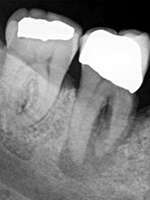

Le kyste est une tumeur bénigne, L'apectomie est une procédure réalisée au cabinet sous anesthésie locale (ablation de l'apex et d'un kyste)